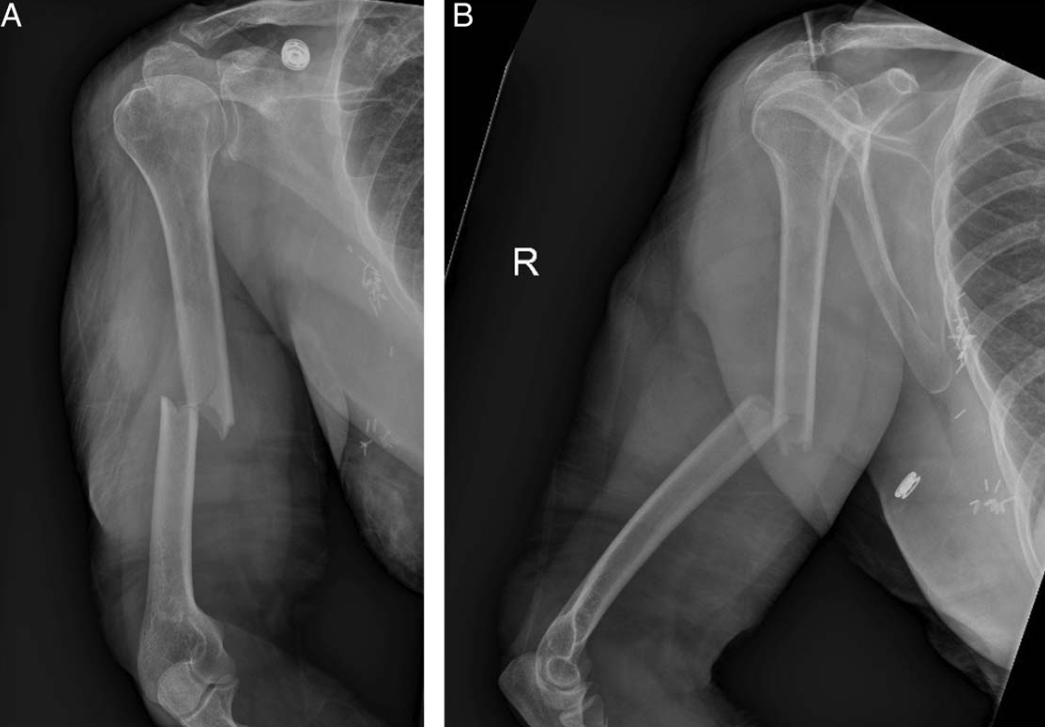

然而,由于其操作简便,并具有良好的固定强度,在骨折内固定中,也有学者单独/辅助使用或临时固定使用,从治疗出发获得了良好的临床效果。如肱骨干骨折复位后的临时固定: